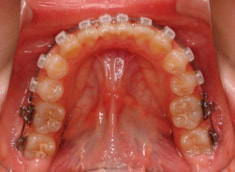

治療後(1年2ヶ月後)